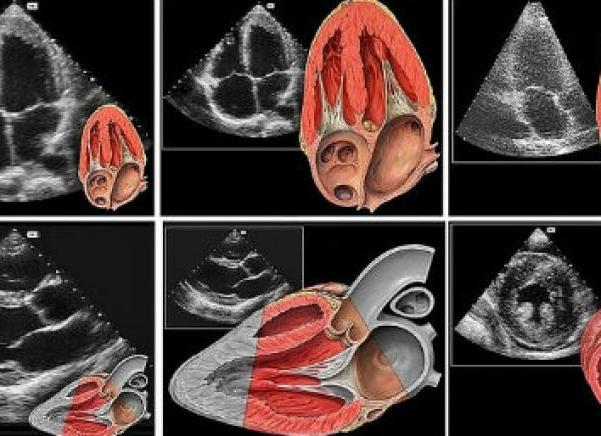

Эхокардиография является комплексным методом исследования, который включает в себя М-режим, В-режим, допплерометрию. Одним из новых направлений УЗИ сердца является использование трехмерной и четырехмерной эхографии.

В-режим — такой доступ, при котором интенсивность принятых сигналов соответствует яркости точек на экране эхокардиографаМ-режим — это разверстка М-режима по времени.На экране регистрируется графическое изображение движения структур сердца, которые пересекаются одним ультразвуковым лучом

Эти методики являются вспомогательными и должны проводиться совместно с В-режимом. Однако несомненным их преимуществом является получение объемного изображения сердца с возможностью оценки гемодинамики.

Это исследование заключается в оценке структур сердца в двухмерном режиме. В этом режиме оцениваются размеры камер в 4-камерной позиции, состояние клапанов, толщина и состояние сердечных стенок, их сократимость. Диагностика должна проводиться полипозиционно, чтобы исключить влияние артефактов.

Исследование сердца методом эхокардиографии дает возможность объективной оценки состояния сердечной мышцы. Специалист визуально определяет степень патологии сердца и на основе показателей нормы выставляет диагноз.

Эхокардиография проводится при помощи специального оборудования, которое состоит из аппарата УЗИ, монитора и специального датчика. Последовательность процедуры следующая. Аппарат УЗИ излучает волны ультразвука, которые, отражаясь от тканей сердца, преобразуются в электроволны. С помощью датчика эти волны улавливаются и визуализируются на экране монитора. Специалист может видеть изображение сердца или его отделов в реальном времени, оценить работу сердца. Также могут быть поставлены дополнительные датчики, считывающие данные о кровотоке, сердцебиении и других показателях. Такие датчики прикрепляются на грудную клетку и спину пациента.

УЗИ диагностика основана на улавливании отражения ультразвуковых волн от тканей организма, поэтому обследование сердца называют эхокардиографией. С помощью УЗИ врач получает на мониторе послойное изображение органа в разных проекциях в режиме реального времени. Он может оценить: